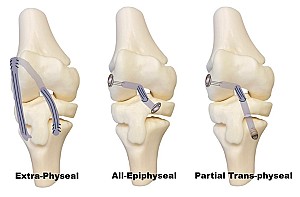

Figura 2: Diversi tipi ri sicostruzione del LCA in pazienti con immaturità scheletrica: extra-fisaria (a), All-epiphyseal (b), trans-fisaria parziale (c)

Esistono diverse tecniche di ricostruzione per pazienti con immaturità scheletrica, che possono essere utilizzate in base all’età e all’entità di crescita rimanente (Figura 2). Nei pazienti prepuberi, la tecnica extra-fisaria utilizza un innesto (di solito la banda ileotibiale o il gracile/semintendinoso) che viene fatto passare attorno al condilo femorale esterno, senza mai creare fori nelle cartilagini di accrescimento [6]. In pratica, il tendine viene passato attorno alla porzione epifisaria del femore e ancorato alla tibia, riproducendo la funzione del LCA senza mantenerne l'anatomia, pur evitando qualsiasi perforazione delle fisi. Nei giovani adolescenti, invece, si impiega la tecnica all-epiphyseal: sotto controllo fluoroscopico vengono praticati due tunnel limitati alle sole epifisi di femore e tibia, senza attraversare mai le cartilagini di crescita [7]. Questo approccio preserva completamente le fisi, riducendo il rischio di arresto di crescita, ma è tecnicamente più complesso e in alcune casistiche è stato segnalato un tasso di complicanze – soprattutto legate a malposizionamenti dei tunnel.

Nei primi stadi puberali si può eseguire una ricostruzione trans-fisaria parziale, risparmiando la fisi femorale ma creando un tunnel tibiale, con un rischio di disturbi della crescita non trascurabili [8]. Per gli adolescenti prossimi alla maturità scheletrica (meno di due anni di crescita residua), la ricostruzione trans-fisiaria Over The Top con tunnel tibiale di piccolo diametro (≤8 mm) risulta generalmente sicura (Figura 3). L’aggiunta di una tenodesi laterale extra-articolare riduce il tasso di fallimento dell’innesto di circa un terzo, a condizione di evitare la violazione delle cartilagini di accrescimento [4].